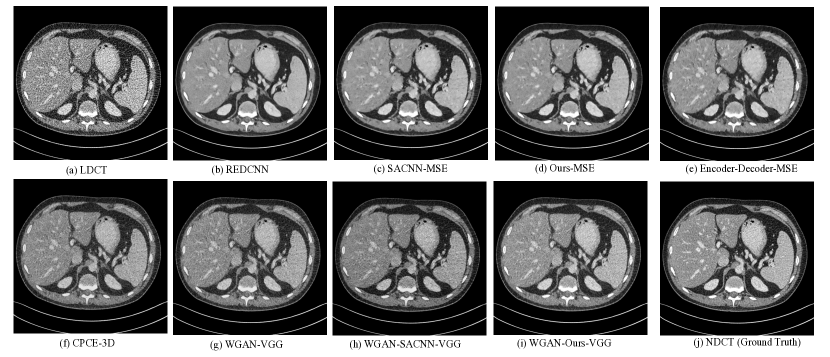

Method Evaluation Metrics PSNR SSIM VIF LDCT 22.1708 0.7512 0.3119 RED-CNN 27.0296 0.8037 0.3801 Encoder-Decoder-MSE 26.8230 0.8001 0.3798 SACNN-MSE 26.8909 0.8004 0.3839 Ours-MSE 26.8953 0.8015 0.3860 WGAN-VGG 25.0128 0.7901 0.3390 CPCE-3D 24.6051 0.7869 0.3193 WGAN-SACNN-VGG 25.2352 0.7902 0.3392 WGAN-Ours-VGG 25.6860 0.8005 0.3449

III-F The comparison of different LDCT denoising models

In this section, we compare our proposed GCN-MIF model with baseline methods on test set. For quantitative performance of denoising results, PSNR, SSIM and visual information fidelity (VIF) [43] are used.The baseline methods include RED-CNN, encoder-decoder-based model (i.e., Baseline4), SACNN, WGAN-VGG [42], and CPCE-3D models. Specially, our proposed GCN-MIF model and SACNN model are trained by two kinds of objectives (including MSE-guided manner and WGAN-VGG framework).

As reported in Table III, under the guidance of MSE, RED-CNN achieves the highest PSNR and SSIM among all methods, which is reasonable as RED-CNN usually generates over-smooth denoising results. It is worthy noting that our proposed method not only has the second highest PSNR and SSIM, but also achieves the best VIF (which can reflect human visual system by using natural statistics models). Thus, the proposed GCN-MIF model balances the noise reduction and structure preservation well. For WGAN-VGG-based models, our proposed model outperforms others with an obvious margin.

The visualized comparison of denoising results is illustrated in the Figure 6. We can roughly observe from Figure 6 that the denoising results generated by our proposed GCN-MIF model (including Our-MSE and WGAN-Ours-VGG) are brighter than others, which reflects the preserving of structural information and contrast ratio.

The zoomed-in region of interest is also presented in the Figure 7. One can have some observations. For MSE-guided models, our proposed model retains more structural information compared with RED-CNN and SACNN-MSE models. For example, the blood vessel (as pointed by green arrow) and subtle detail (as pointed by blue arrow) can be still noticed by our proposed method. Although encoder-decoder-MSE model achieves good structure preserving, the ability of noise suppression is very limited (as shown in red circle). For WGAN-VGG-based models, due to the introduction of explicit non-local information, SACNN and our proposed model have better performance for noise reduction (as circled in the dark background area). Compared with SACNN, our proposed model maintains the subtle structure more. As pointed by blue circle, the denoising result by SACNN is difficult to be noticed.